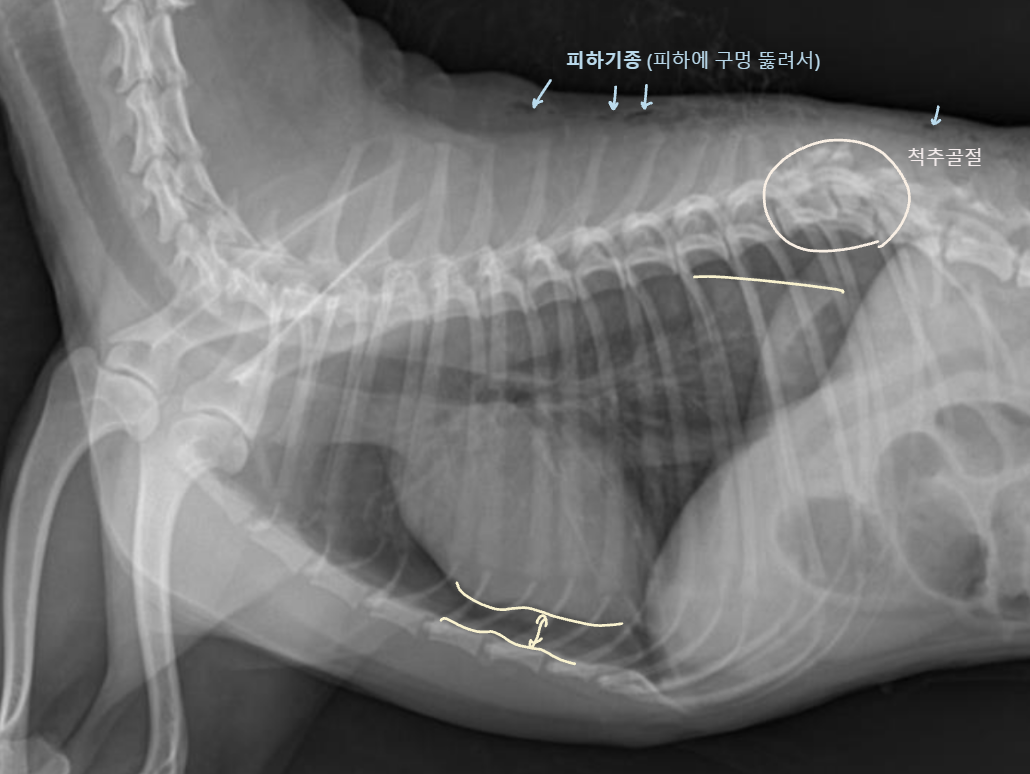

4. Pleural Space

| Pleural effusion (ํ์) | Pneumothorax (๊ธฐํ) | |

|---|---|---|

| ํ๊ฐ(pleural cavity)์ ๋ฌผ์ด ์ฐฌ ๊ฒ (ํ์ ์ฐจ๋ฉด โ ํ์์ข ) | ํ๊ฐ์ ๊ณต๊ธฐ๊ฐ ์ฐฌ ๊ฒ (ํ์ ์ฐจ๋ฉด โ ํ๊ธฐ์ข ) | |

| Radiographic signs interlobar fissure ๋๊ป๊ฒ ๊ด์ฐฐ๋๊ณ , ํ๋ฒฝ์ด ๋จ์ด์ ธ ๋๊ฐ ๊ฒ์ฒ๋ผ ๋ณด์ | Radiographic signs ์ฌ์ฅ์ด ๋ ์๊ณ , ํ๊ฐ ์ชผ๊ทธ๋ผ๋ฆ | |

| - Interlobar fissure widening - Lung retraction - Pleural wall thickening - Scallop sign - Cardiac effacement - Blunt angle | - Retraction of pleural surface - Collapsed lung (โ opacity ์ฆ๊ฐ) | |

![]() | ![]() | |

![]() ![]() | ![]() ![]() | |

![]() |